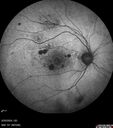

BRAO - plaques in vessels - GIF video of FA3 views78 year old female with vision loss for 1 week and old macular scar. Images show BRAO with plaques and FA shows occlusion.Oct 13, 2025

BRAO - plaques in vessels - GIF video of FA2 views78 year old female with vision loss for 1 week and old macular scar. Images show BRAO with plaques and FA shows occlusion.Oct 13, 2025